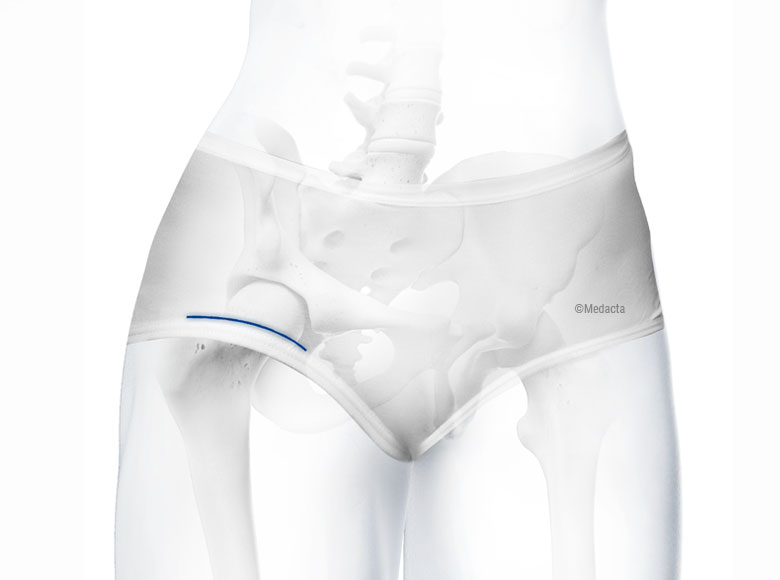

A bikini incision total hip replacement is a form of direct anterior hip replacement surgery where the incision is made in line with the natural skin crease of the groin, similar to where a bikini bottom would sit. This technique aims to reduce visible scarring while maintaining the benefits of the anterior approach, including muscle-sparing access and the potential for faster recovery.

While the term ‘bikini incision’ refers primarily to the cosmetic placement of the surgical cut, it is part of a broader effort to enhance recovery, reduce soft tissue trauma, and improve patient satisfaction after hip replacement surgery.

The incision is placed along the natural groin crease, resulting in a scar that is less noticeable, especially when wearing swimwear or underwear. - Muscle-sparing approach